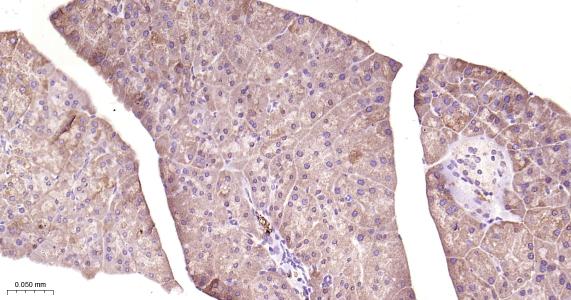

Paraformaldehyde-fixed, paraffin embedded Human Pancreas; Antigen retrieval by boiling in sodium citrate buffer (pH6.0) for 15 min; Antibody incubation GSK-3 Beta Monoclonal Antibody, Unconjugated (bsm-63070R) at 1:200 overnight at 4°C, followed by conjugation to the bs-0295G-HRP and DAB (C-0010) staining.

Paraformaldehyde-fixed, paraffin embedded Rat Pancreas; Antigen retrieval by boiling in sodium citrate buffer (pH6.0) for 15 min; Antibody incubation GSK-3 Beta Monoclonal Antibody, Unconjugated (bsm-63070R) at 1:200 overnight at 4°C, followed by conjugation to the bs-0295G-HRP and DAB (C-0010) staining.